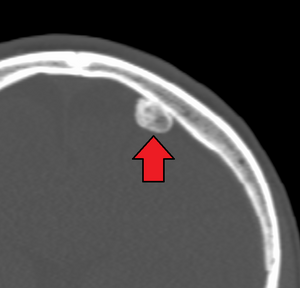

![]() | |

| CT scan showing an osteoma growing on inside of skull bone | |